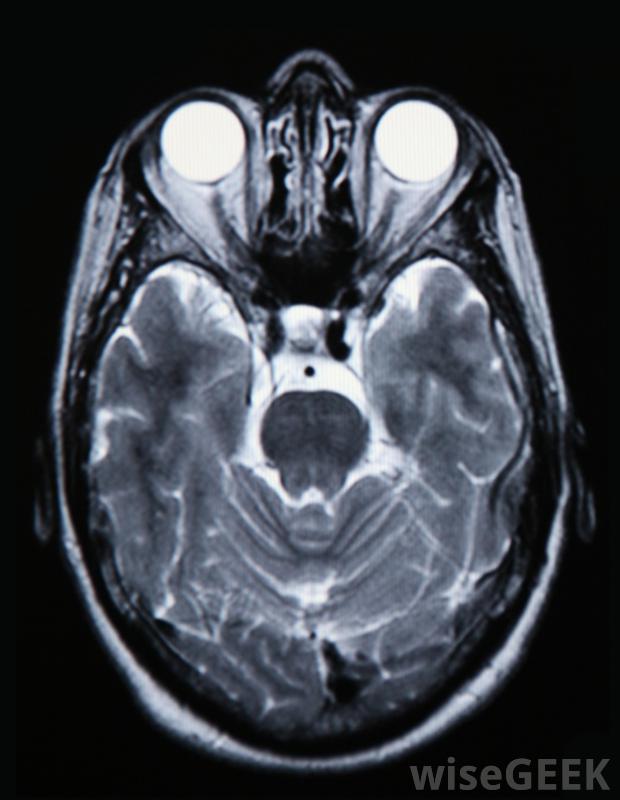

脑部扫描将向医生显示是否存在脑挫伤。有些症状更为特定于脑挫伤,而不是由头部的撞击。由于对大脑的撞击,这个人的眼睛或耳朵周围可能会有瘀伤另外,从病人鼻子、嘴或耳朵流出的透明液体表明大脑的盖子已经破裂,伴随着脑挫伤,液体从头部流出。儿童,尤其是那些不能说话的孩子,可能是孩子脑部挫伤后经常出现的脑部挫伤,也可能是孩子脑部受创后出现的一种不同程度的瘀伤,也可能是由于孩子的脑部不断受挫伤而引起的也不要对通常能吸引他的注意力的玩具或其他他平时喜欢的活动感兴趣。如果一个人在头部受到重击后出现上述症状,他需要立即就医。通常情况下,病人会被密切观察,直到医生能扫描出是否有脑挫伤。医生也可以要求做血液检查,它可以揭示患者大脑任何潜在损伤的重要细节。除非由合格的医学专业人士进行治疗,否则脑挫伤可能是致命的。

没有医疗干预,不可能明确地说出一个人的大脑是否有瘀伤。